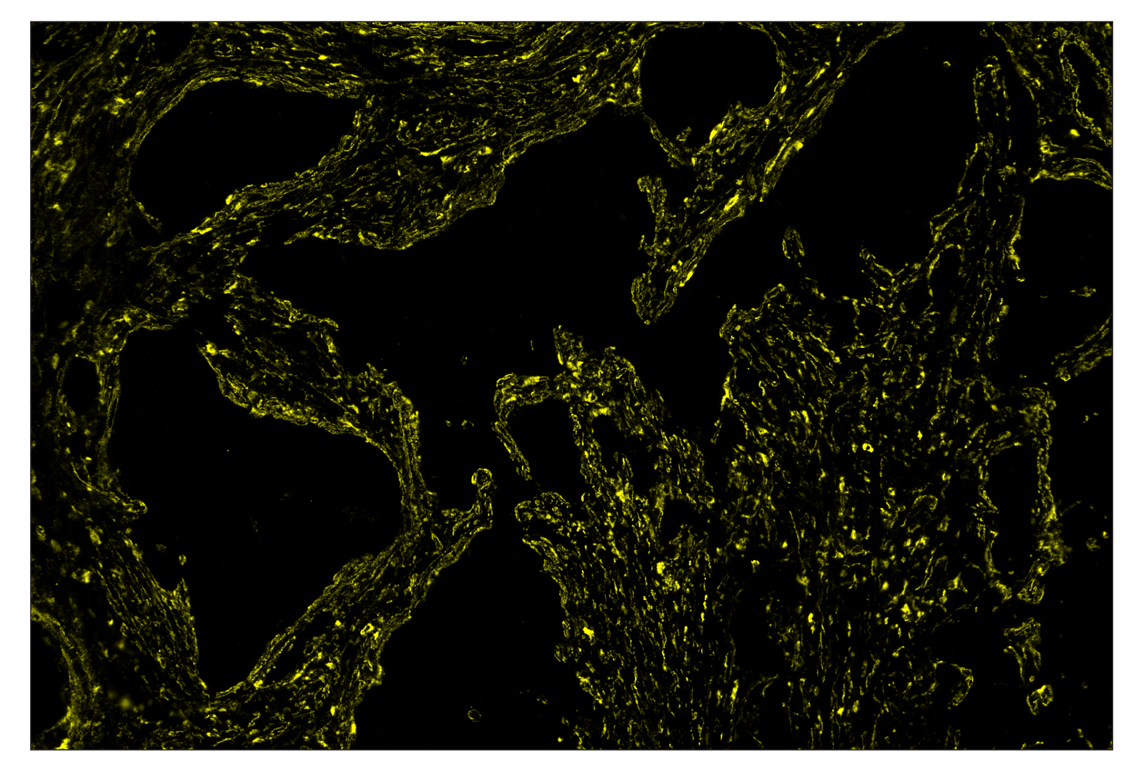

SignalStar™ immunohistochemical analysis of paraffin-embedded human squamous cell lung carcinoma using α-Smooth Muscle Actin (D4K9N) & CO-0024-488 SignalStar™ Oligo-Antibody Pair #76133 (green). All fluorophores have been assigned a pseudocolor, as indicated. Staining was performed on the BOND RX by Leica Biosystems.

Immunohistochemistry Image 2: alpha-Smooth Muscle Actin (D4K9N) & CO-0024-488 SignalStar<sup>™</sup> Oligo-Antibody Pair